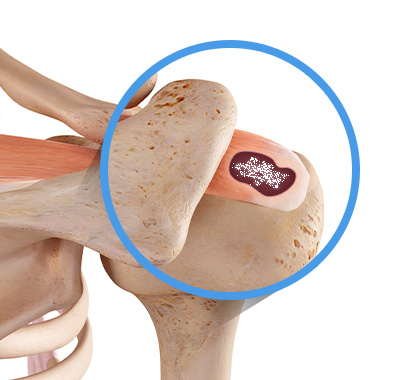

석회성건염은 칼슘 퇴적물이 관절의 힘줄에 침착되며 염증과 통증을 유발하는 질환입니다.

석회성건염은 어깨, 팔꿈치, 고관절, 무릎, 손목. 발목 등 다양한 관절에 발생합니다.

빠르고 근본적인 비수술 치료법

석회성건염으로 통증이 극심하다면 체외로 제거하는 것이 빠른 치료입니다.

비수술 또는 수술로 제거하느냐의 차이일 뿐입니다.